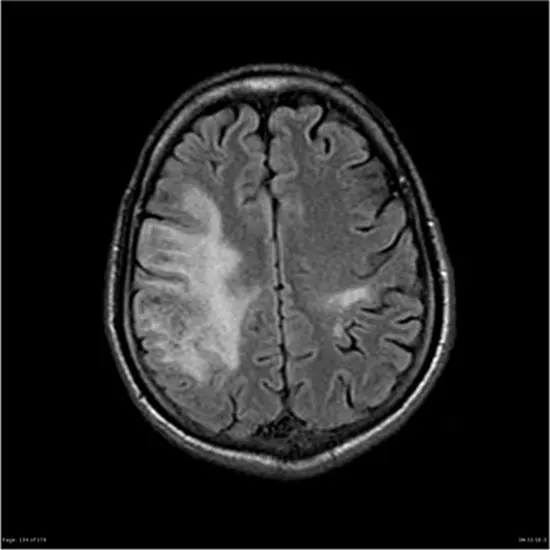

Progressive multifocal leukoencephalopathy (PML) is a rare and potentially fatal neurological condition caused by the JC virus, a type of virus that typically does not cause disease in healthy individuals. PML occurs most commonly in people with weakened immune systems, such as those with HIV/AIDS, certain cancers, or those taking immunosuppressive medications.

PML is characterized by damage to the white matter of the brain, leading to progressive neurological symptoms such as weakness, difficulty speaking, visual changes, and cognitive decline. These symptoms can worsen over time and may eventually lead to coma and death.

MRI Brain with contrast 11500 5750